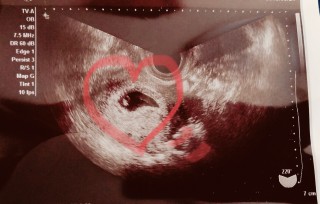

6w2dの時のエコーです。 小さい心拍も同時に確認できました! 形が丸くないのが不安でしたが、婦人科の先生が問題ないと言ってくれました!

6w2dのエコーです。 ピコピコ心拍が確認できて、 まだこんなにちっちゃいのに生きてるんだと思ったら可愛くて仕方ありませんでした。 旦那さんはまだ豆粒みたいでよくわからないみたいですが、やっぱりお腹にいるとなんとなくわかり可愛くて仕方ないです! 次は9wです!ドキドキです。